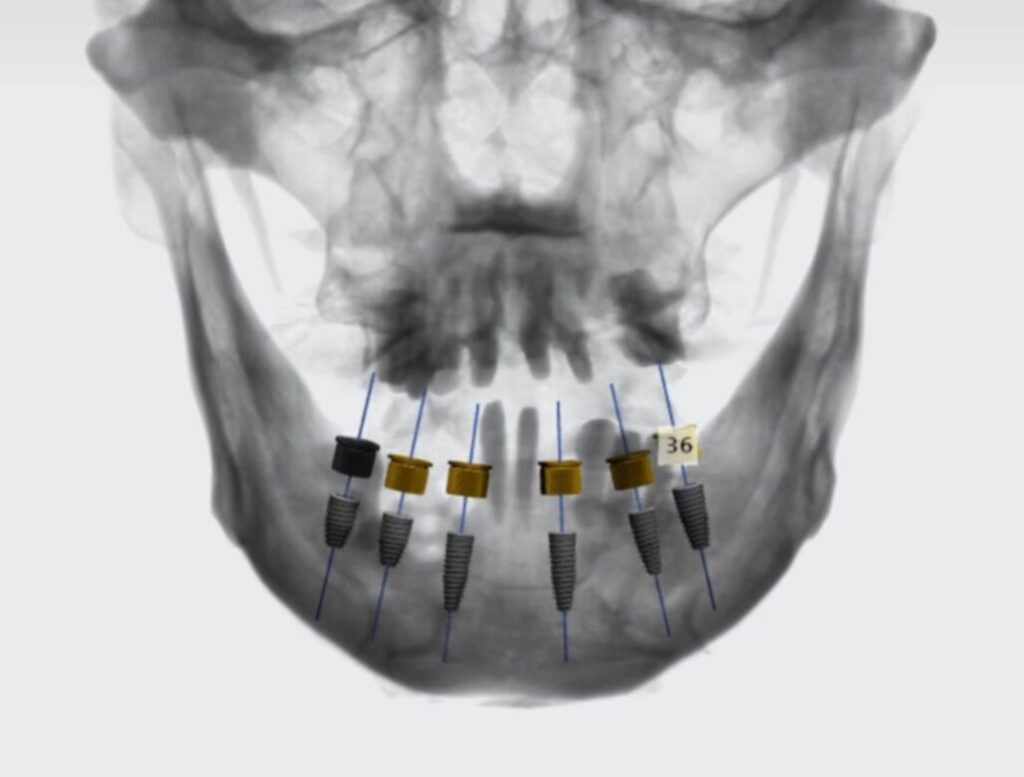

Tomografia 3D (CBCT)

Evaluación de hueso,

anatomía y planificación de implantes cuando

corresponde.

Diseño y Planificacion Digital

Primero definimos el

resultado, luego lo ejecutamos con precisión clínica.